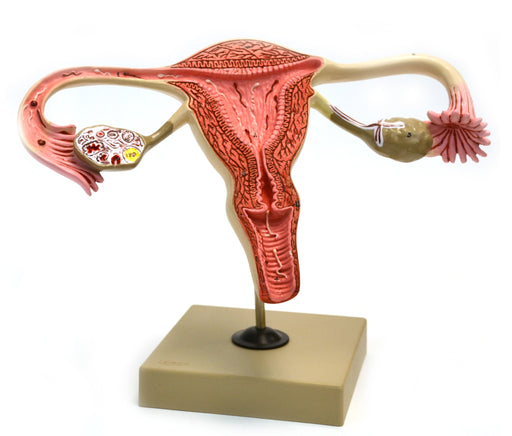

Model, Human, Female Reproductive, Ovary

3 x life size 12" x 5.5" x 8" Internal structure of human female reporductive system displayed in aproximently 3 times life size. Shows Vagina, ...

View full detailsAM360AS -

Eisco 3x Life-Size Human Female Reproductive System, Cross Section

Enlarged approx. 3 times. Enlarged approx. 3 times. This model represent the frontal section through female genital organ. Mounted on base. Numbere...

View full detailsAM0360 -